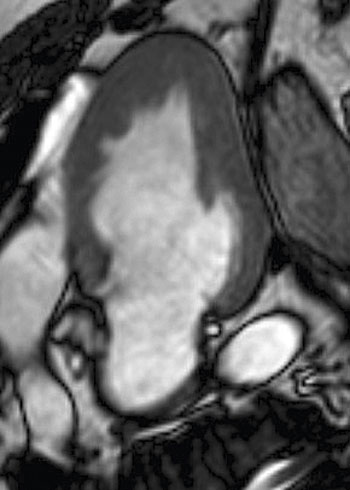

Bilddiagnostik med bland annat ultraljud och doppler

Ultraljudsundersökning av hjärtat påvisar ­hypertrofi – oftast i kammarseptum, men alla delar av hjärtat kan påverkas (Figur 3, 4 och 5). Det förekommer en variant med enbart apikal hypertrofi. Med dopplerundersökning kan förhöjda hastigheter över vänsterkammarens utflödesregion påvisas i vila hos ungefär en tredjedel, medan hos ytterligare cirka en tredjedel förhöjd gradient (tryckskillnad) kan provoceras fram genom fysiologisk belastning, Valsalvas manöver eller läkemedel. Den metod som numera rekommenderas är fysiologisk belastning på cykelergometer eller gångmatta, vilket är av värde om ingen gradient ses vid vila då anamnesen indikerar en dynamisk gradient.

Figur 3. Ekokardiografi, parasternal långaxel, vid septal hypertrofisk kardio­myopati.